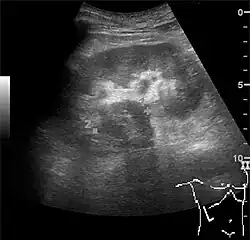

Complex cysts can have membranes dividing the fluid-filled center with internal echoes, calcifications or irregular thickened walls. The complex cyst can be further evaluated with Doppler US, and for Bosniak classification and follow-up of complex cysts, either contrast-enhanced ultrasound (CEUS) or contrast CT is used (Figure 6). The Bosniak classification is divided into four groups going from I, corresponding to a simple cyst, to IV, corresponding to a cyst with solid parts and an 85–100% risk of malignancy.[1] In polycystic kidney disease, multiple cysts of varying size in close contact with each other are seen filling virtually the entire renal region. In advanced stages of this disease, the kidneys are enlarged with a lack of corticomedullary differentiation (Figure 7).[1]

Figure 6. Complex cyst with thickened walls and membranes in the lower pole of an adult kidney. Measurements of kidney length and the complex cyst on the US image are illustrated by '+' and dashed lines.[1]